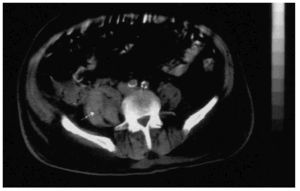

Paciente varón de 78 años con antecedentes de enfermedad coronaria multivaso, infarto de miocardio de cara inferior, diabetes mellitus tipo 2, dislipemia y procesos catarrales frecuentes asociados a hiperreactividad bronquial que ingresó en nuestro servicio por un cuadro de angina inestable. Su tratamiento habitual consistía en aspirina (100 mg/día) y diltiacem en preparado retard (180 mg/12 h). A su ingreso la exploración física no mostró datos de interés salvo una presión arterial de 160/80 mmHg; el hemograma con recuento plaquetario y el estudio de coagulación fueron normales; la bioquímica no presentaba datos relevantes: troponina I, 0,2 ng/ml (normalidad, < 1,5 ng/ml), y fracción de la MB-masa de la creatin-fosfocinasa: 1,2 ng/ml (normalidad, < 3,2 ng/ml). Se inició tratamiento con atenolol oral, nitroglicerina en perfusión intravenosa, enalapril oral, aspirina y enoxaparina a las dosis recomendadas para los síndromes coronarios sin elevación del ST, en nuestro caso 80 mg subcutánea cada 12 h. En los tres días siguientes presentó varios episodios anginosos y desarrolló un IAM no Q, una insuficiencia renal con creatinina de 2 mg/dl con un aclaramiento de 66,7 ml/min y un cuadro de hiperreactividad bronquial, que se resolvió en 48 h con broncodilatadores inhalados y corticoides intravenosos. En el séptimo día de estancia en nuestra unidad, en los hemogramas seriados se detectó una caída de las cifras de hemoglobina hasta 8,5 g/dl con aparición de equimosis en el flanco abdominal derecho, por lo que se le solicitó una tomografía axial computarizada abdominal en la que se evidenció un hematoma retroperitoneal que infiltraba el músculo psoas derecho (fig. 1). Decidimos mantener tratamiento antitrombótico con aspirina disminuyendo la dosis de enoxaparina s.c. a 20 mg/día y se le transfundieron dos concentrados de hematíes, tras lo cual el paciente permaneció estable. Se le realizó coronariografía que mostró una enfermedad coronaria multivaso no revascularizable, con buena función ventricular, por lo que fue dado de alta en tratamiento con aspirina, atenolol, nitratos tópicos y amlodipino.

Figura 1. Hematoma retroperitoneal (flecha) de pequeño volumen que infiltra el músculo psoas derecho.